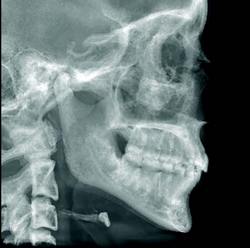

CBCT devices may be used for traditional forms of radiography, in addition to advanced 3-D volumetric renderings. Conventional cephalometric measurements may be obtained through 3-D volumetric images by rendering the image as a 2-D projection resembling a radiograph or a panoramic image. It is also possible to digitize cephalometric points in 3-D, resulting in the introduction of multiple analyses.

Non-conventional renderings are also realized using CT data. In fact, X-ray projections that are non-physical are possible. For example, a cephalogram can be created where the patient’s neck vertebrae have been omitted. The advantage of this type of rendering is that in a conventional ceph, the vertebrae may obfuscate the dentition, whereas in a non-conventional rendering, they do not.